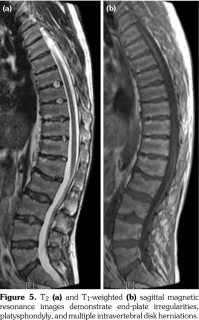

Physical examination revealed decreased range of motion in shoulders, wrists, metacarpophalangeal, proximal IP, distal IP, and ankle joints. In particular, the IP, metacarpophalangeal and metatarsophalangeal joints had bony enlargements, mild tenderness and flexion contractures; however, no signs of inflammation like redness, effusion, or other signs of synovitis (Figure1). The patient also had mild spinal scoliosis, significant thoracolumbar kyphosis, and pectus excavatum deformity. Furthermore, he had saddle nose deformity, bilateral floppy pinna and audiovestibular dysfunction (sensorineural hearing loss and tinnitus) (Figure 2). The rest of the systemic examination was unremarkable.

Radiographs of the hands showed enlargement of metaphyses, flattening of epiphyses, and narrowing of joint spaces with no erosions. Lateral radiograph of the foot revealed bilateral large ossified trigonum attached to the talus (mega os trigonum) (Figure 3). Radiographs of the spine showed increased kyphosis, generalized platyspondyly particularly at the thoracolumbar junction, and irregularity of the vertebral end- plates (Figure 4). Magnetic resonance imaging of thoracolumbar spine demonstrated irregularity in vertebral end-plates, multiple disk herniations, and platyspondyly (Figure 5). Dynamic contrast- enhanced magnetic resonance imaging of the wrist did not reveal any signs of synovial inflammation.